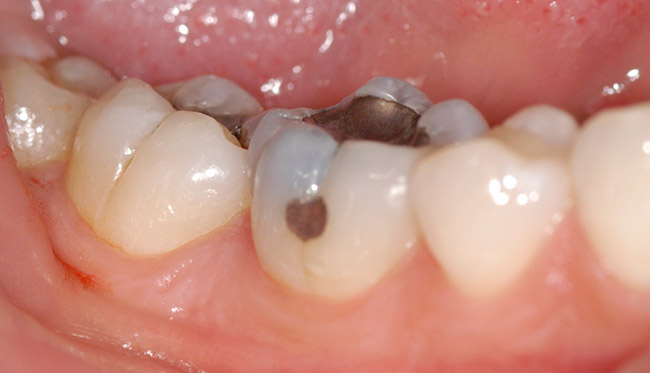

Contemporary resin-based composites have addressed the many problems they have experienced since their introduction. Fillers have made them stronger, more resistant to wear, and increased their polishability. Fillers have also reduced the stress induced during photopolymerization.22 Although shrinkage on photopolymerization has been decreased, it still remains a significant problem with Class 1 restorations on posterior teeth23 (Figure 1).

Figure 1   Two posterior molars with marginal failure and recurrent decay.

Figure 1